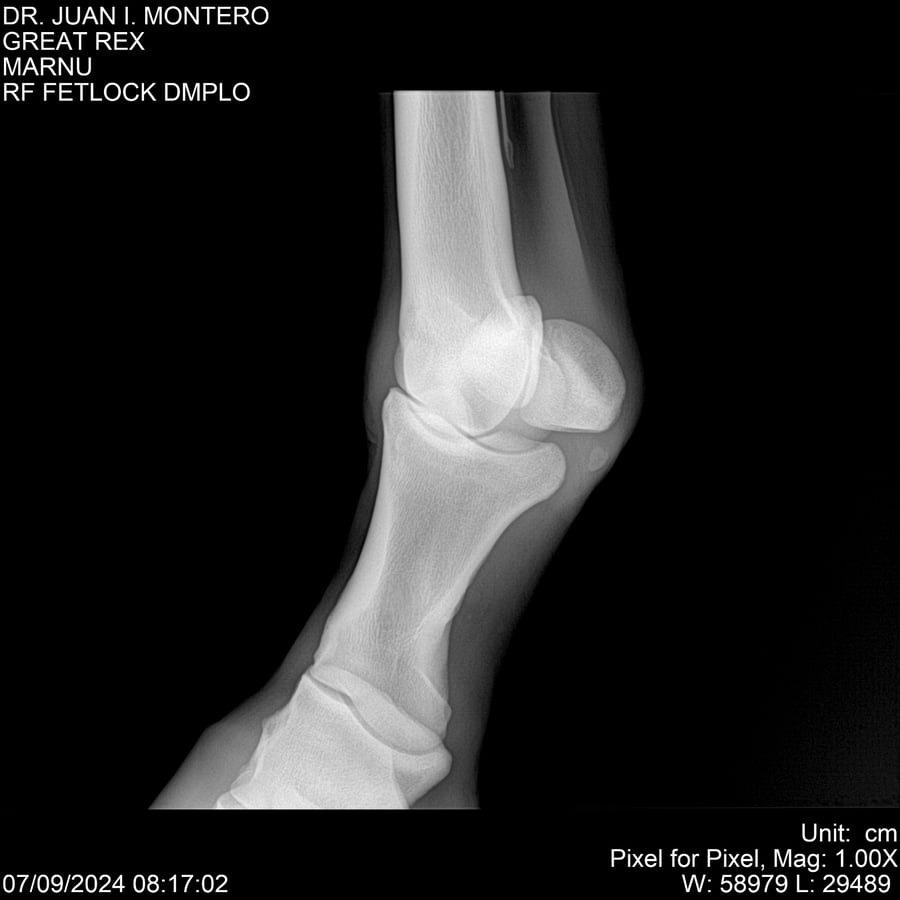

LOTE 4, GREAT REX Lote Anterior Volver al remate Lote Siguiente Ficha Contacto Montevideo - Ficha del Lote Identificador: #282518 Categoría: Yeguarizos Montevideo - 66 Visualizaciones ClicData Contacto Empresa: Abelenda N. R., Walter Hugo Nombre*: Teléfono* : E-mail* : Mensaje Enviar Registrese gratis Este contenido Exclusivo está disponible sólo para usuarios registrados Ingresar